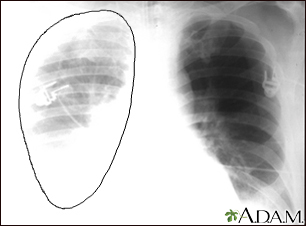

Aortic rupture - chest x-rayBackAortic rupture - chest x-rayAortic rupture (a tear in the aorta, which is the major artery coming from the heart) can be seen on a chest x-ray. In this case, it was caused by a traumatic perforation of the thoracic aorta. This is how the x-ray appears when the chest is full of blood (right-sided hemothorax) seen here as cloudiness on the left side of the picture. E-mail FormEmail ResultsName:Email address:Recipients Name:Recipients address:Message: